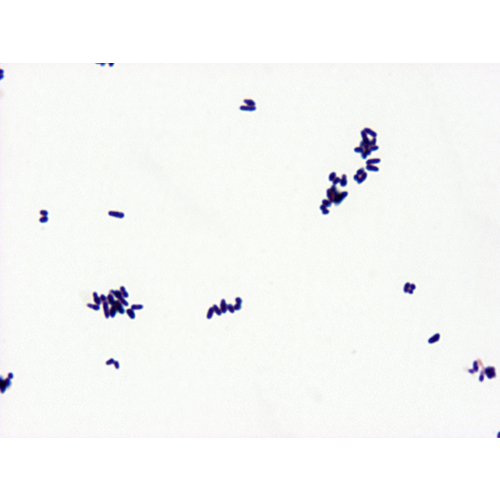

Bacillus Cereus

Large Gram positive rods, chains